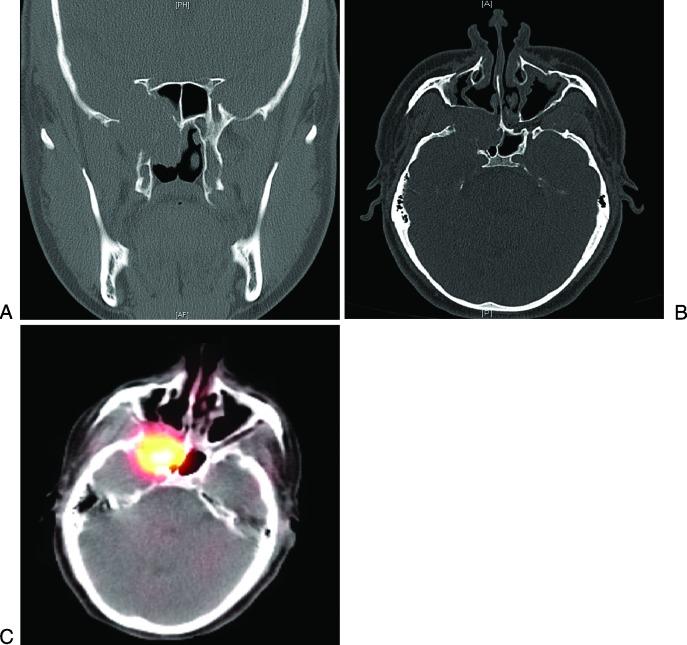

Sinonasal paragangliomas are very uncommon neuroendocrine tumors that can present as skull base lesions. Functional paragangliomas are exceedingly rare. They can be associated with genetic mutations that have been associated with increased risk of head and neck paragangliomas. We present a case of a rare functioning sinonasal paraganglioma of the skull base in a patient with distant history of prior abdominal paragangliomas. The patient underwent subtotal endoscopic resection of the skull base lesion limited by carotid encasement of the tumor. They were treated with postoperative adjuvant radiation and therapeutic metaiodobenzylguanidine (MIBG) therapy. Genetic testing revealed succinate dehydrogenase B (SDHB) mutation. Skull base paragangliomas are rare tumors that may preclude complete surgical resection. (131)Iodine-MIBG can be used as adjuvant therapy in postoperative external beam radiation and in MIBG avid tumors. Long-term follow-up is needed given locally aggressive nature of these tumors, especially for patients with history of genetic mutations such as SDHB mutations as recurrent paragangliomas may develop.

鼻窦副神经节瘤是非常罕见的神经内分泌肿瘤,可表现为颅底病变。功能性副神经节瘤极为罕见。它们可能与基因突变有关,而这些基因突变与头颈部副神经节瘤风险增加相关。我们报告一例罕见的功能性鼻窦颅底副神经节瘤病例,患者既往有腹部副神经节瘤病史。患者接受了因肿瘤包绕颈动脉而受限的颅底病变内镜下次全切除术。术后接受辅助放疗及治疗性间碘苄胍(MIBG)治疗。基因检测显示琥珀酸脱氢酶B(SDHB)突变。颅底副神经节瘤是罕见肿瘤,可能无法完全手术切除。碘-131 MIBG可作为术后外照射放疗及MIBG摄取阳性肿瘤的辅助治疗。鉴于这些肿瘤具有局部侵袭性,尤其是有SDHB突变等基因突变病史的患者可能发生复发性副神经节瘤,因此需要长期随访。